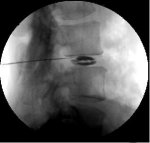

Discography is a diagnostic procedure, not a treatment. X-ray dye is injected into the spinal disc(s) and an x-ray (called a "discogram") is taken. The discogram may be normal or may show tears (fissures) in the lining of the disc. The results of discography can be used to plan spinal surgery or IDET (IntraDiscal ElectroThermal Therapy) or Nucleoplasty.

When a normal disc is injected, you will feel a sense of pressure, not pain. When an abnormal disc is injected, you will feel pain. It is important to try to determine if the pain you are feeling is your “typical pain” or not. When each disc is injected, you will be asked if it is painful, where you feel the pain and whether it is in the same area as your usual pain.